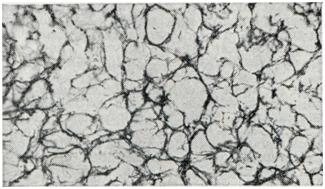

Рис. 2.

Сеть ретикулиновых волокон в ангиоретикулеме (импрегнация по Пердрау; ×200).

Митозы обычно не встречаются. Иногда обнаруживаются тучные, плазмоцитоидные клетки. Могут наблюдаться очажки экстрамедуллярного кроветворения. В стенках сосудов с помощью импрегнационных методик выявляется характерное для ангиоретикулемы обилие ретикулиновых волокон, местами охватывающих и группы клеток межсосудистой ткани (рис. 2). Край опухоли образован петлями капилляров, переходящих в прилежащую мозговую ткань, и поэтому неровен. В опухоли или ее участках может преобладать какой-либо один из компонентов — сосудистый или клеточный.